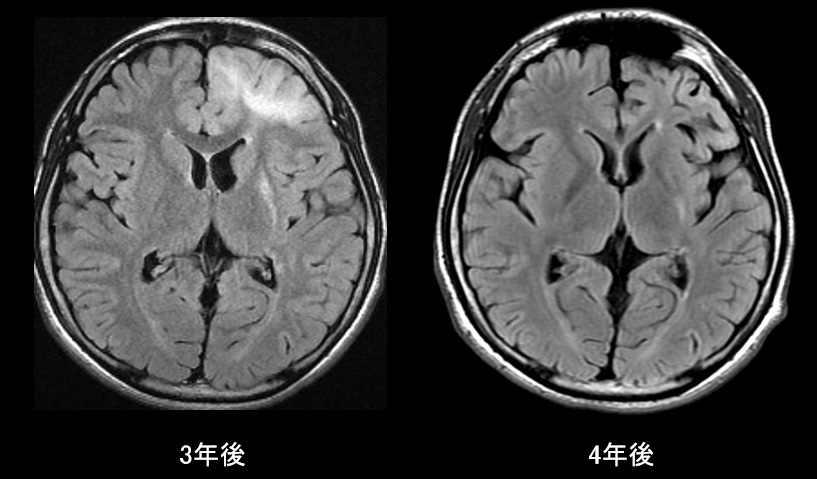

初診から3年後のMRで左前頭葉のT2WI/FLAIR高信号域の拡大が認められたため、脳生検を行った。

→Fragment of cerebral tissue with reactive gliosis

(Gliomaは否定的)

経過3

腫瘍が除外されたため、ステロイドパルス施行。